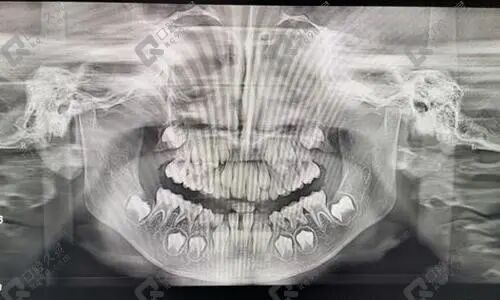

戴牙套是矫正牙齿先天错颌畸形的一项常规和主流的口腔正畸手段,可以有效纠正龅牙、地包天、深覆合、牙齿拥挤、牙列不齐、牙缝稀疏等成年人及青少年错颌畸形问题。

因为我不是一个特别能坚持的人,了解到戴牙套要一年多到两年左右,所以考虑了很久。几番对比咨询后去了当地有名口腔医院面诊,医生给我出了好几个正畸方案,沟通了拔4颗牙齿后矫正,然后采用隐形矫正,因为年纪大了好面子~

我的牙齿开始是有点错乱拥挤,前牙突出,现在整完牙已经有一年多的时间了,一直有坚持佩戴矫正保持器,并没有出现别人所说的反弹的情况,整个人面部焕然一新,朋友都以为我去悄悄整容了呢~